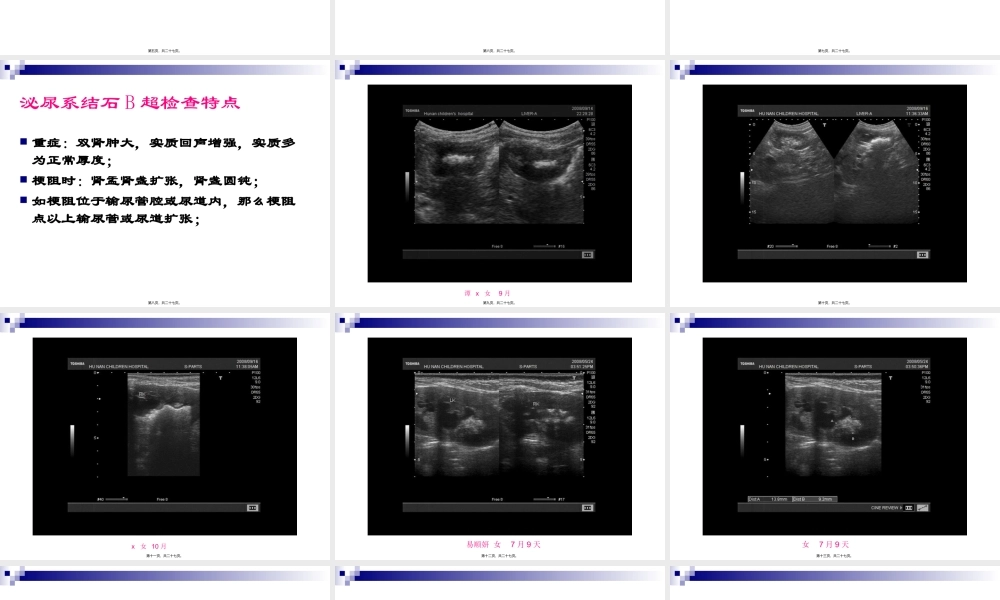

2、本站所有内容均由合作方或网友上传,本站不对文档的完整性、权威性及其观点立场正确性做任何保证或承诺!文档内容仅供研究参考,付费前请自行鉴别。

3、如文档内容存在违规,或者侵犯商业秘密、侵犯著作权等,请点击“违规举报”。

碎片内容

蜗牛文库的最新文档

二年级数学下册其中检测卷二年级数学下册其中检测卷附答案#期中测试卷.pdf

10.00金币

0下载